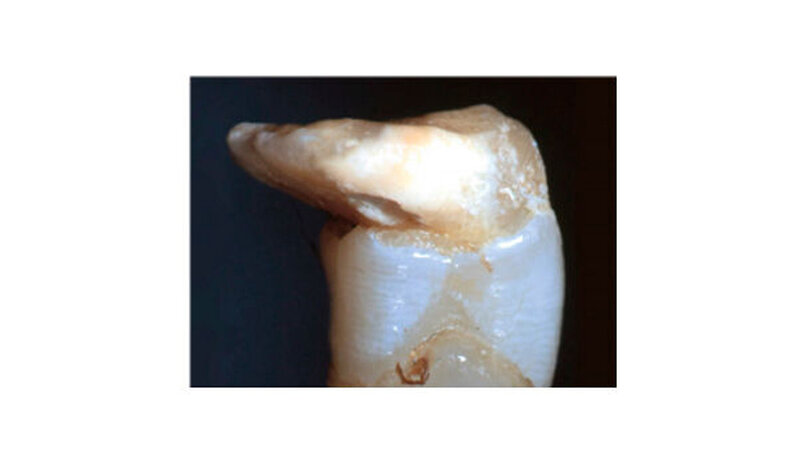

Alles, was bereits vollständig mineralisiert ist, ist nicht oder kaum betroffen. Bei einer axialen Stauchung des bleibenden Zahnkeims durch die Milchzahnwurzel kommt es zur sogenannten kalizotraumatischen Linie, bei einer erheblichen nicht-axialen Stauchung zur Verlagerung der bereits mineralisierten Zahnhartsubstanz. Die nach dem Unfall weiter fortschreitende Mineralisation des Zahns folgt nicht etwa der neuen Lage des Zahns sondern wählt den Weg, der ihr genetisch vorgegeben wurde - unabhängig von der Lage und Position des bereits mineralisierten Anteils.

Die Folge ist ein mehr oder weniger ausgeprägter scharfer Knick im Zahn. Davon abzugrenzen ist die ebenfalls unfallbedingte vestibuläre Wurzelkrümmung (Vestibular root angulation), die eine Biegung der Zahns/der Wurzel und keinen Knick aufweist. Diese entsteht häufiger nach Milchzahnavulsion, wo der Zahnkeim langsam eine andere Durchbruchsrichtung einschlägt. Ursache ist unter anderem eine lokale Fibrosierung im Bereich der Milchzahnalveole.

Dilazeration (Abb. 1 bis 7) kann zur Durchbruchsstörung des betroffen Zahns führen. Fast immer sind auch Farb- und Formanomalien des Schmelzes zu beobachten. Die Erhaltungsmöglichkeit solcher Zähne hängt primär von der Schwere und Lokalisation der Missbildung, aber auch vom Grad der Farb- und Strukturanomalie ab. Malformationen im mittleren oder apikalen Wurzeldrittel sind ohne Einfluss auf den dentogingivalen Verschluss und haben in der Regel wenig Einfluss auf den Zahnerhalt - die Pulpa bleibt hier in den meisten Fällen vital.